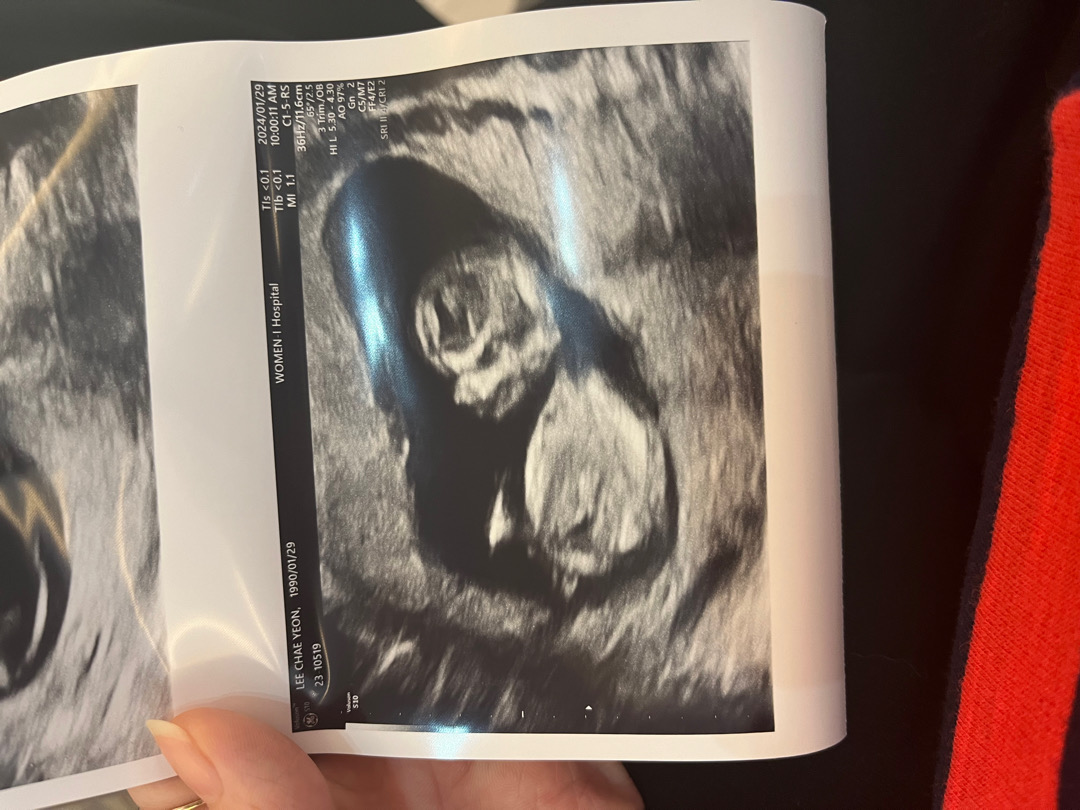

12주각도법

어떻게보이시나용?

병원에서 딸일가능성이있어보인다더라구요ㅋㅋ